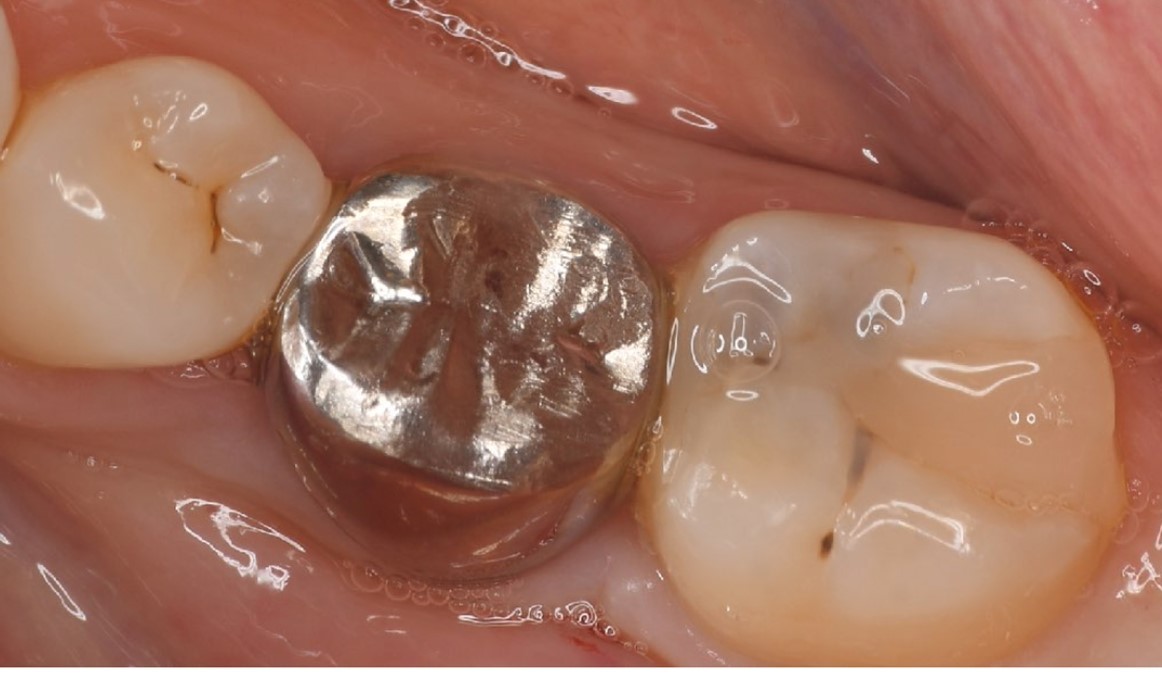

A 27-year-old female patient came to us with discomfort in the right lower jaw (Figure 1). Her primary symptoms were pain in the lower right tooth when biting and discomfort associated with not being able to chew well with the lower left single denture. The patient was married and had one young child, and previously received dental treatment in China, then had returned to Japan for childbirth and early childcare. The patient was a nonsmoker with moderate plaque control and medical history taking revealed no problems. In clinical and radiographic examinations, a root fracture was observed on tooth #46, which had been endodontic ally treated and restored with a full-cast metal crown. Periodontal probing revealed a pocket depth of 8 mm on the buccal center side of the tooth. No pain was detected with percussion and mobility of the tooth was normal. (Figure 1, Figure 2, Figure 3).

Figure 3.Preoperative intraoral findings. A metal crown was inserted at #46 and bleeding on probing during the periodontal pocket examination was noted.

Full metal crowns were inserted for #46 and #47. Pathological mobility and bleeding on probing were not seen, and the transplanted tooth showed good function.